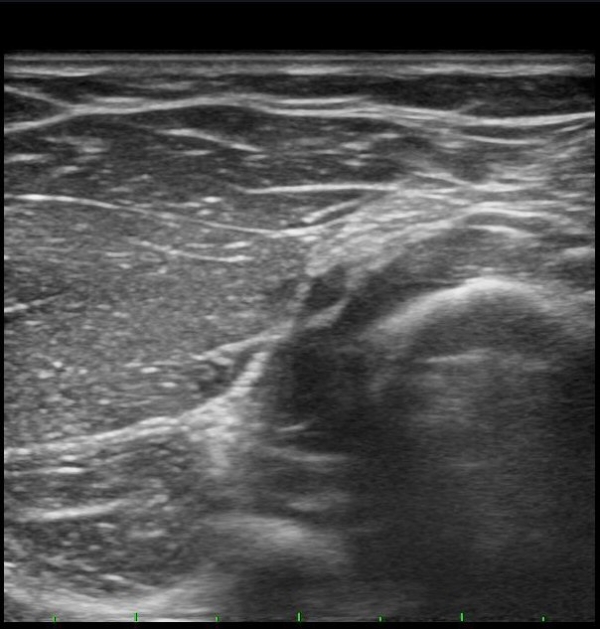

ŽÃËÀÚÀ» ¸»´ÜÀ¸·Î À̵¿ÇÏÀÚ Èİñ°£½Å°æÀÌ È¸¿Ü±Ù ±ÙÀ§ºÎ¿¡¼­ Àú¿¡ÄÚ ºÎÁ¾À» º¸ÀÓ(±×¸² 2).

¾Æ·§ÆÈÀ» ȸ³» À§Ä¡¿¡¼­ Èİñ°£½Å°æ Á¾´Ü¸é°Ë»ç¸¦ ½ÃÇàÇÏ´Ï Èİñ°£½Å°æÀÌ µÎ ȸ¿Ü±Ù »çÀÌ¿¡¼­ ¾Ð¹Ú¹Þ°í ȸ¿Ü±Ù ±ÙÀ§ºÎ¿¡¼­ Àú¿¡ÄÚ ºÎÁ¾ÀÌ °üÂûµÊ(±×¸² 4, 5).